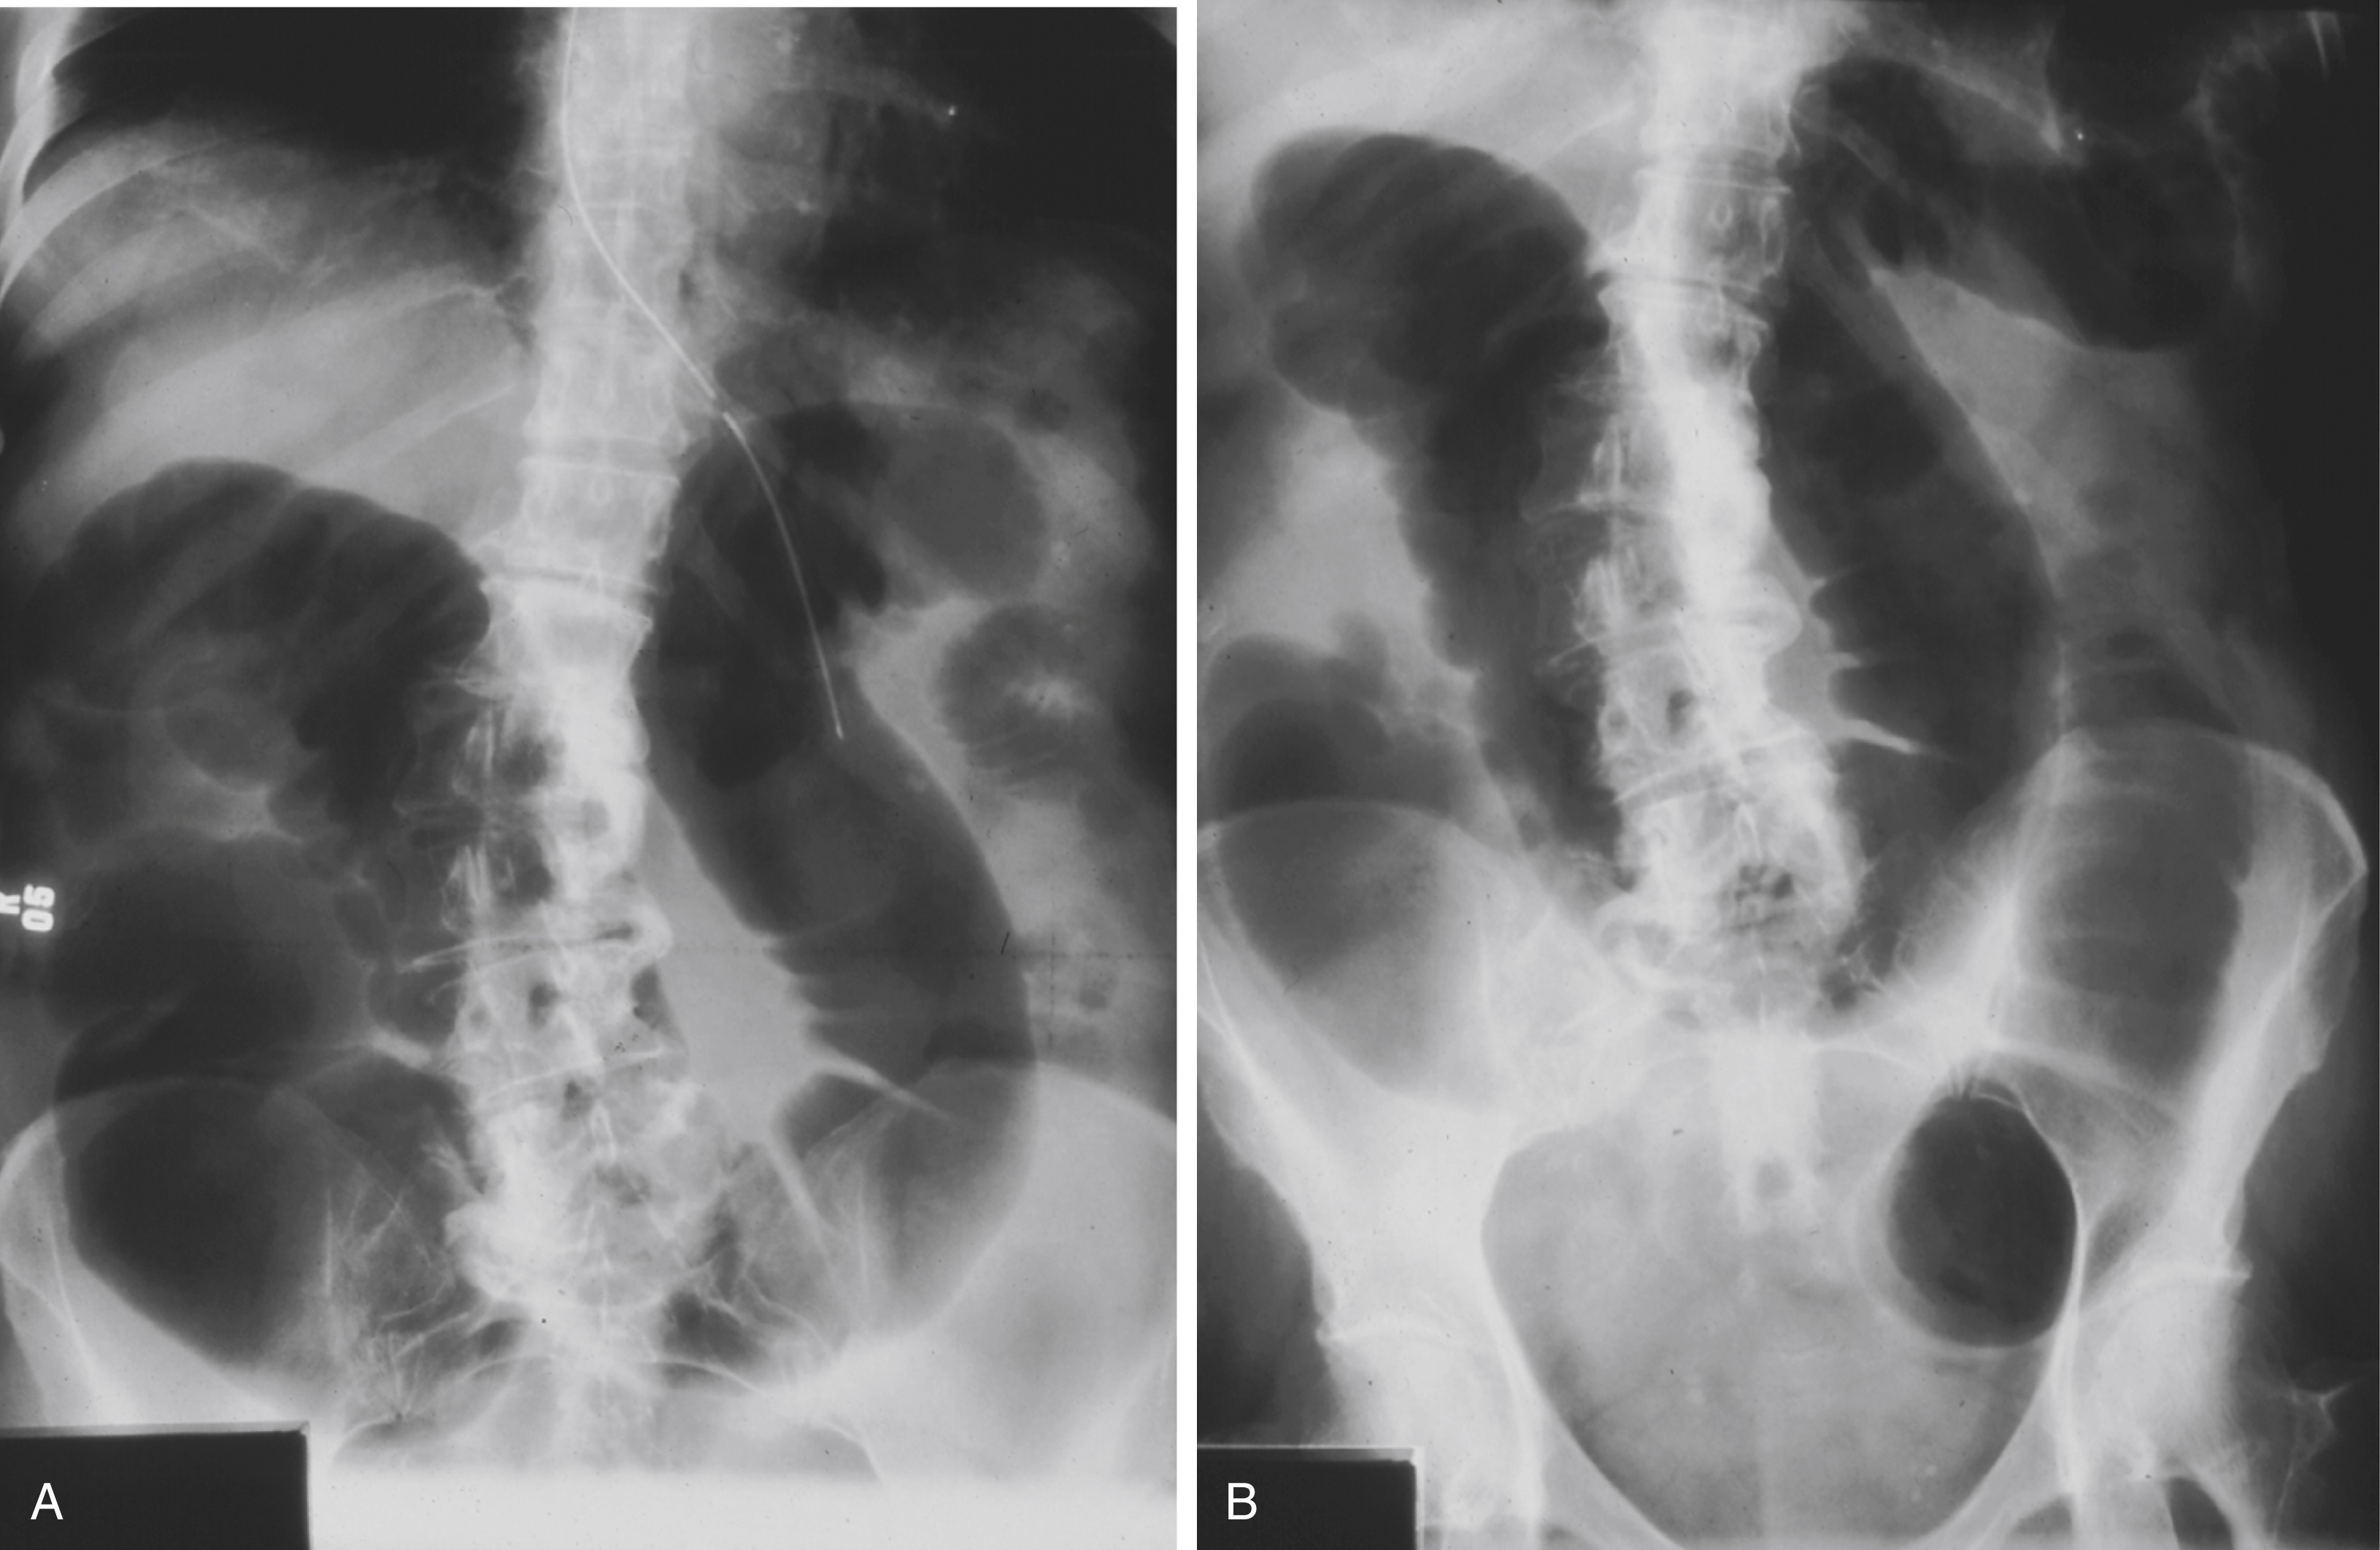

Both supine and upright plain films are advised for the workup of LBO and ACPO ( Fig. 81.4 ). A distended colon (>6 cm diameter) is the hallmark of LBO, although the small bowel may be distended as well (>3 cm diameter) if the ileocecal valve is incompetent. A cecal diameter >6 cm is abnormal and when >12 cm is associated with a higher risk of perforation, although perforation has been known to occur at smaller diameters. The actual location and cause of the LBO are usually not evident on plain films.

Plain Radiographs Showing Large Bowel Obstruction at the Sigmoid Colon Caused by Carcinoma.

(A) Upright view. (B) Supine view.